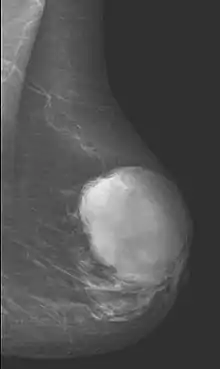

Radiographical imaging is the first-line test for identifying a phyllodes tumor.[11] Despite their propensity to grow rapidly and deform the overlying breast tissue, approximately 20% of phyllodes tumors can present as a nonpalpable mass on screening mammography.[12] Other imaging tools used to assess the size and spread of a phyllodes tumor include ultrasound and magnetic resonance imaging (MRI).[11] None of these imaging tools are definitive tests for differentiating a phyllodes tumor from a benign fibroadenoma.[13] Phyllodes tumors can only be diagnosed histologically, as they tend to have many overlapping features with other breast masses on physical examination and radiological imaging.[11]